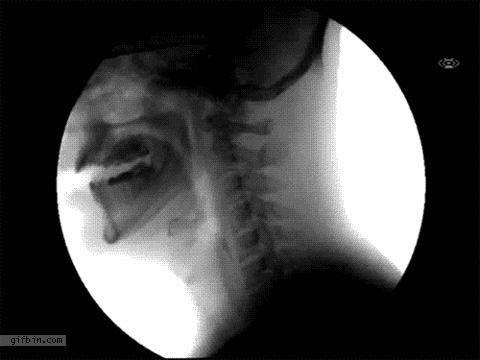

물 마실 때 X-Ray